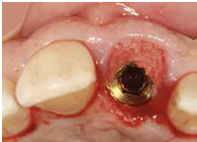

並於100/10/25將中間兩顆植體做二階接出

由於前後植體的高低差距太大,決定將中間兩顆高度較為一致的植體假牙做連結,但前後兩顆做單顆假牙的設計。

100/11/21 補綴完成

目前植體周圍的組織都很理想健康並追蹤中。